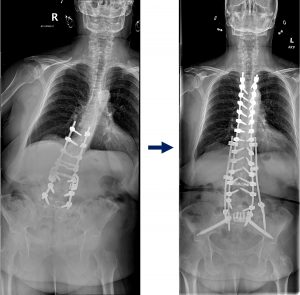

Singh diagnosed her with rigid spinal deformity and severe sagittal and coronal plane imbalance. The only way forward was a complex surgical reconstruction.

He explained every step of the operation: entering through her abdomen to remove old hardware, carefully breaking and realigning her spine, and reinstrumenting from her upper thoracic vertebrae (T4) to her pelvis (S2). The surgery would last more than 13 hours.

Today, Krasniak can stand tall and walk without assistance. “I can look people in the eye again, without tilting my head up,” she says. “My lower back pain is gone. I feel like a completely different person.”

Flat back syndrome, in particular, is a challenging condition that develops when the natural curve of the lower spine is lost, often after multiple prior surgeries. This creates a rigid deformity that forces patients into a stooped position, leading to severe imbalance, pain, and loss of quality of life.